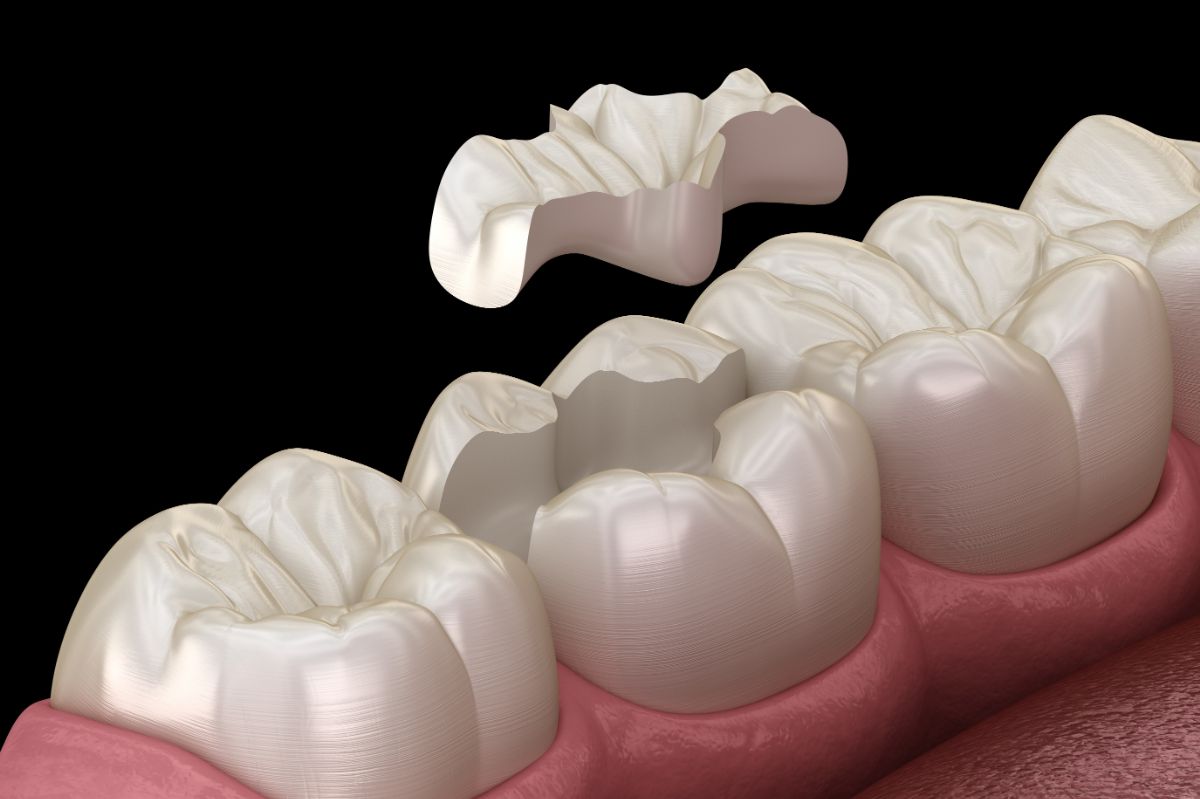

セラミック・

ジルコニア治療の特徴

特徴

セラミックよりも硬く、割れにくいため奥歯の治療の選択肢にもなる。

共通するメリットとして、金属を使っていないため、金属アレルギーの方でも選択できる素材であること、密着性が高く、二次むし歯を防ぎやすいことなどが挙げられます。

当院では、ご希望に応じてセラミック、またはジルコニアの詰め物や被せ物をご提案しています。

- 型取りと製作

- 装着と調整